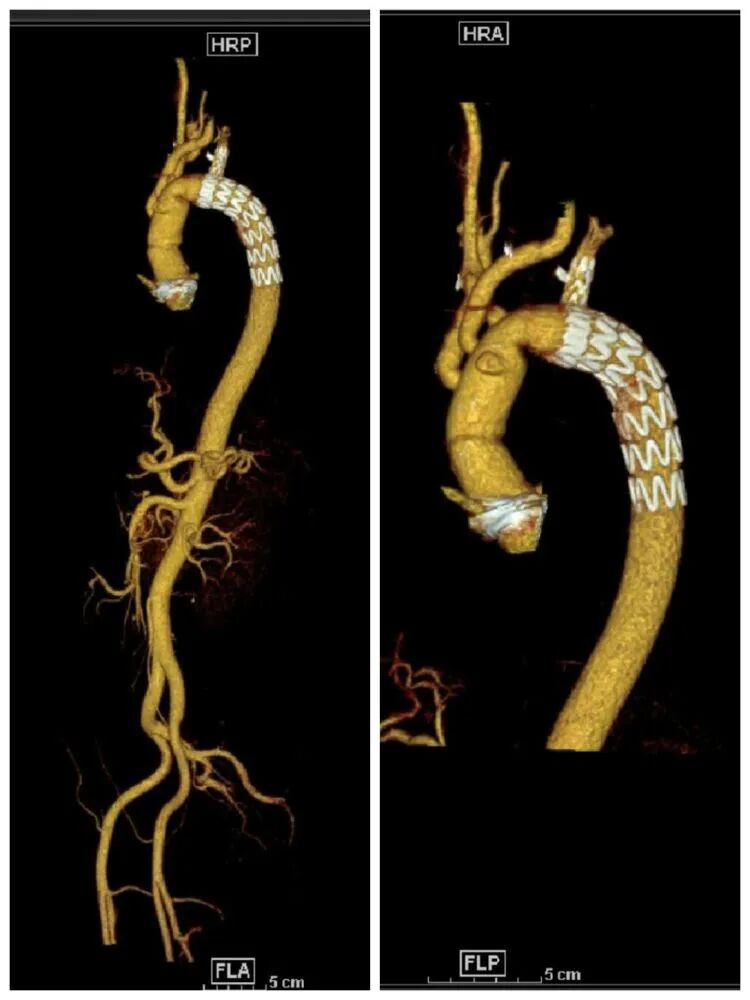

术前胸腹主动脉CTA示主动脉夹层(Stanford A型)

经家属同意和积极术前准备,于2023年8月17日顺利实施了升主动脉置换术+主动脉弓替换术+“象鼻”支架植入术+左侧单发椎动脉重建术,手术于19时10分顺利开始,这仅仅是第一台夹层手术结束后1个小时,术中探查患者左侧椎动脉起自主动脉弓,我们成功重建了左侧单发的椎动脉,最终成功完成了手术。

术后复查胸腹主动脉CTA示主动脉形态良好,重建的椎动脉通畅。